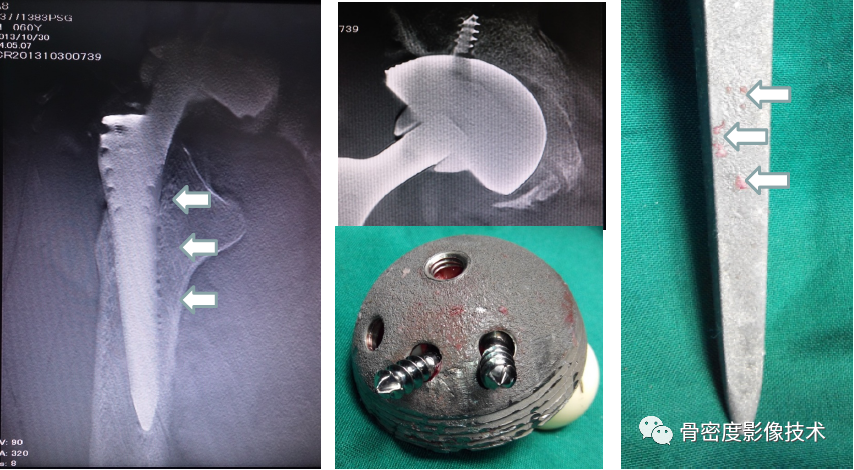

图5 股骨颈骨质量术前评估联合股骨、膝关节置换等术后评价

图6 髋臼骨质量术前评估联合臼杯置换术后评价

备注:图片由北京积水潭医院提供